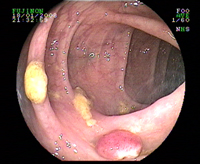

Polype sessile

Polype sessile du colon

Polype sessile dysplasique